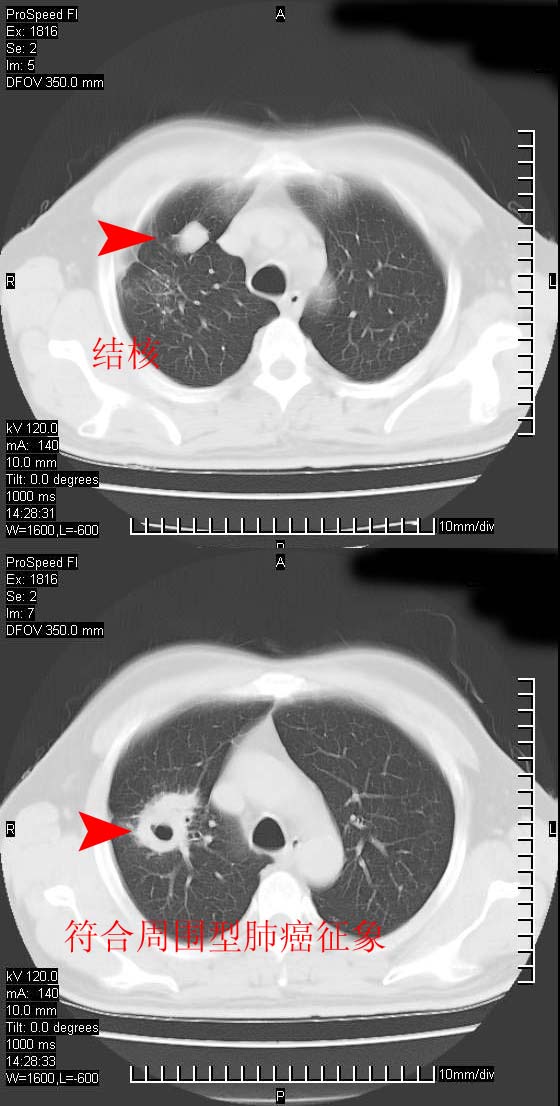

男性,50 ,肺结核9年,咳嗽,胸痛一周。右上肺见一厚壁空洞,周边有点样钙化,胸膜牵拉,洞壁较光整。诊断结核性空洞。有癌性的可能吗? 余肺野无异常,没有上传。

考虑为周围性肺癌可能性大

这人应该诊断为肺ca,因为9年的结核密度绝对不是这样!

结核有可能,肺癌待排。空洞的前上还方见一软组织结节影。

部分层面见空洞为近似新月形,洞壁内缘尚规整且近肺门侧,周围见索条影、卫星灶,结合病史,首先考虑肺tb可能大。

9年的结核应该呈现多形态病灶,该病例只能见到少许纤维索条影,似乎与结核的演变不太相符。空洞内壁不光整,外侧伴有胸膜粘连,考虑癌性空洞可能性大,期待结果。